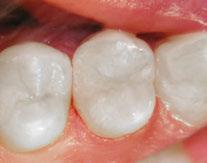

The 5-year-old patient featured in this case study did not benefit from early oral care and had multiple carious lesions. Considering the young age, high caries risk, and the uncertainty of compliance with follow-up appointments, I wanted to restore and seal all teeth in one visit. One quadrant is shown in this case study. The carious lesion on tooth J (65) was cavitated and prepared, restored, and sealed. Tooth I (64) was non-carious and would only be sealed (Figure 1).

I chose Activa™ Kids Bioactive-Restorative and Activa Presto (Pulpdent) as restorative materials for this case because I have seen excellent clinical results over time with these bioactive materials. Continuous release and recharge of calcium, fluoride, and phosphate from these restoratives are beneficial in the fight against decay long into the future.

Choosing restoratives based on ease of use and the ability to work quickly was important in this case. All restorations were completed under general anesthesia in one appointment. There were wear facets on the occlusal surfaces of the molars, so it was important to use a material that would have some flexibility and resistance to fracture. The innovative composition of Activa Kids includes an elastomeric monomer or “rubberized” component that absorbs forces and was an ideal filling material. Activa Presto shares similar properties, and it was convenient to use as an occlusal surface sealant for this patient.

Tooth J (65) was bulk-filled with Activa Kids. For this fast injection technique, I place the dispensing tip at the floor of the preparation and extrude the material without removing the tip until the preparation is completely filled (Figure 5). I like to do some minor manipulation of the filling material with hand instruments to create anatomy, as well as to ensure the material is flush with the surface of the preparation, and no air is trapped inside. Activa Kids is dual-cure, ideal for bulk filling, and can be cured with all lights. A thin topcoat of Activa Presto was placed as a sealant on the entire occlusal surface of teeth I and J (64 and 65) (Figure 6). Figure 7 shows the final clinical situation.

Figure 1 (left): Caries lesion on tooth J (65). Figure 2 (center): Preparation of tooth J (65) and abraded occlusal surface of tooth I (64). Figure 3 (right): Selective etch of enamel Figure 4 (left): Bonding agent is applied to both teeth I and J (64 and 65). Figure 5 (right): The preparation is filled with ACTIVA Kids Figure 6 (left): A thin topcoat of ACTIVA Presto is applied to the occlusal surfaces of teeth I and J (64, 65). Figure 7 (right): Final result